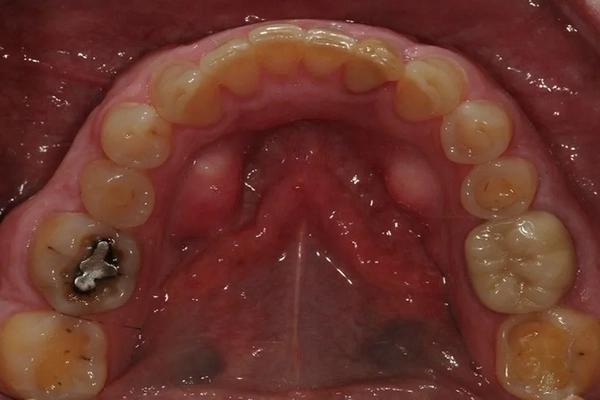

Before

Mercury-Free Dentistry Before and Afters at Suite Dental